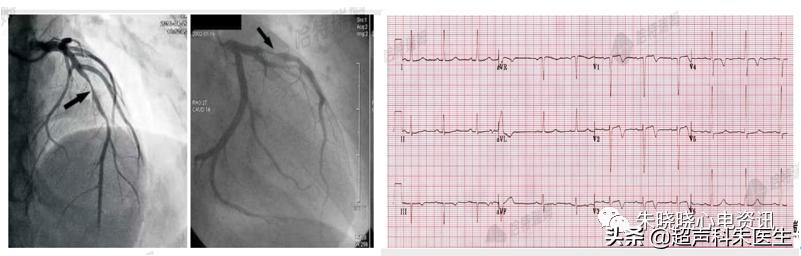

病例4:Wellens综合征

如图20所示,67岁男性,因“胸痛持续性加重4小时”入院。冠脉造影示:前降支重度狭窄。

图20:Wellens综合征

1982年, Wellens等人提出Wellens现象,即前降支近端狭窄者存在着特征性的T波改变。此后,人们将其命名为Wellens综合征。

1型Wellens综合征: ST段位于等电位线,或呈水平型或稍弓背抬高 (<1 mm) ,紧接对称性倒置T波,通常见于V2~V3导联,也可见于V1~V4导联。

2型Wellens综合征: 主要为V2~V3导联,T波呈正负双相。

图21:Wellens综合征的分型